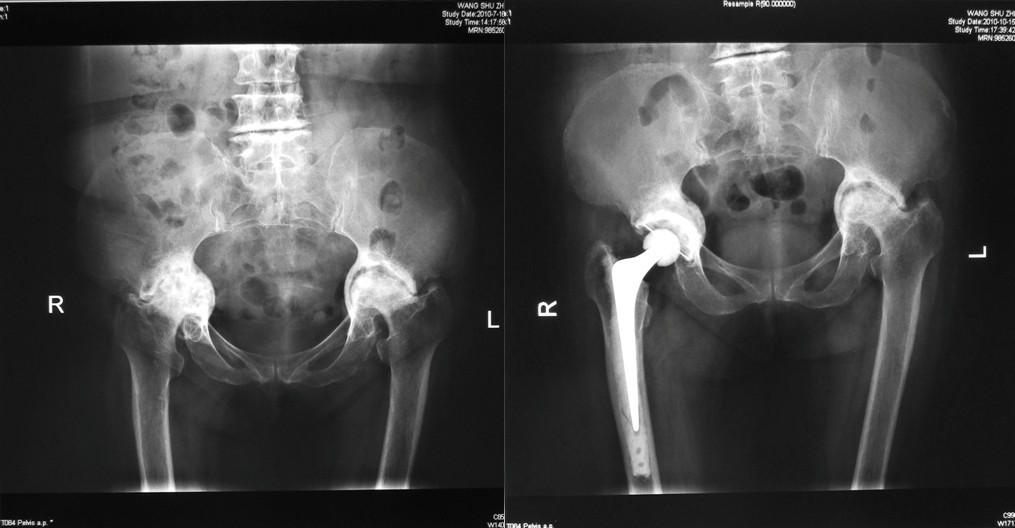

自2004年7月至2006年5月间我院采用颗粒骨打压植骨技术结合骨水泥全髋关节置换术治疗的各型髋臼骨缺损患者15例,其中男性患者4例,女性患者11例,右侧10例,左侧5例。平均年龄55.3岁(36~72岁),随访4-6年。其中髋臼发育不良合并髋关节骨性关节炎7例,髋臼骨溶解假体松动翻修5例,类风湿性关节炎2例,髋关节陈旧结核假性融合1例。术前、术后髋关节功能评价采用Harris评分系统。术前、术后摄髋关节X线片,观察髋关节假体的位置和植骨愈合情况。

⑴Ⅰ型缺损:髋臼发育不良合并骨性关节炎,髋臼上缘Ⅰ型骨缺损,以金属网包含上缘缺损螺钉固定后,打压植骨,三代骨水泥技术全髋关节置换。

患者髋关节Harris评分由术前的平均35.8分提高到术后的平均81.3分,平均随访4-6月,植骨愈合良好, X线片上一例出现透亮带,无症状予继续观察,未行再次翻修,没有发生伤口或深部感染。无坐骨神经麻痹和髋关节脱位发生。